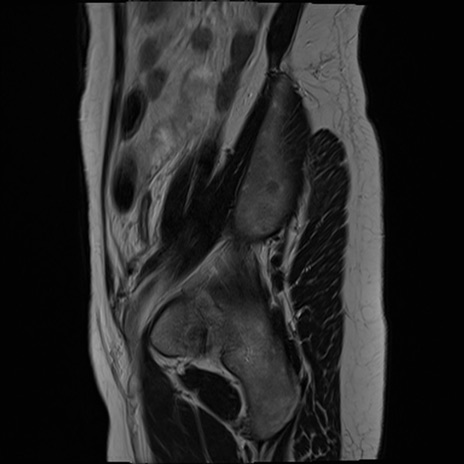

MRI(4日後)

DWI/ADC